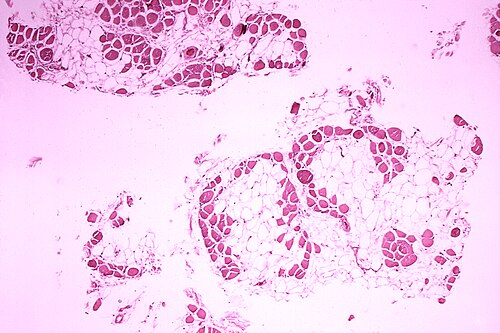

Dr. Edwin P. Ewing, Jr. · Public domain · source

DiagnosisGenetic testing, elevated creatine kinase, muscle biopsy

The disorder is caused by mutations in the dystrophin gene located on the X chromosome, leading to absence or severe reduction of dystrophin, a cytoskeletal protein that links the sarcolemma to the extracellular matrix. Loss of dystrophin disrupts the dystrophin-associated protein complex, increasing sarcolemmal permeability, calcium influx, and activation of proteases and inflammatory cascades, which culminate in myonecrosis and replacement with fibrofatty tissue. Molecular mechanisms considered in therapeutic development include nonsense mutations amenable to read-through compounds, frame-shifting deletions targeted by exon-skipping antisense oligonucleotides, and gene-replacement strategies using viral vectors to deliver micro- or mini-dystrophin constructs.

Clinical evaluation integrates family history, pattern of weakness, and characteristic signs with laboratory testing such as markedly elevated serum creatine kinase levels. Definitive diagnosis is achieved through genetic testing including multiplex ligation-dependent probe amplification, next-generation sequencing panels, and deletion/duplication analysis of the dystrophin gene; muscle biopsy with immunohistochemistry or Western blot for dystrophin may be used when genetic results are inconclusive. Cardiac assessment with echocardiography and cardiac MRI, pulmonary function testing including spirometry and overnight oximetry, and neurodevelopmental evaluation inform baseline status and surveillance planning.